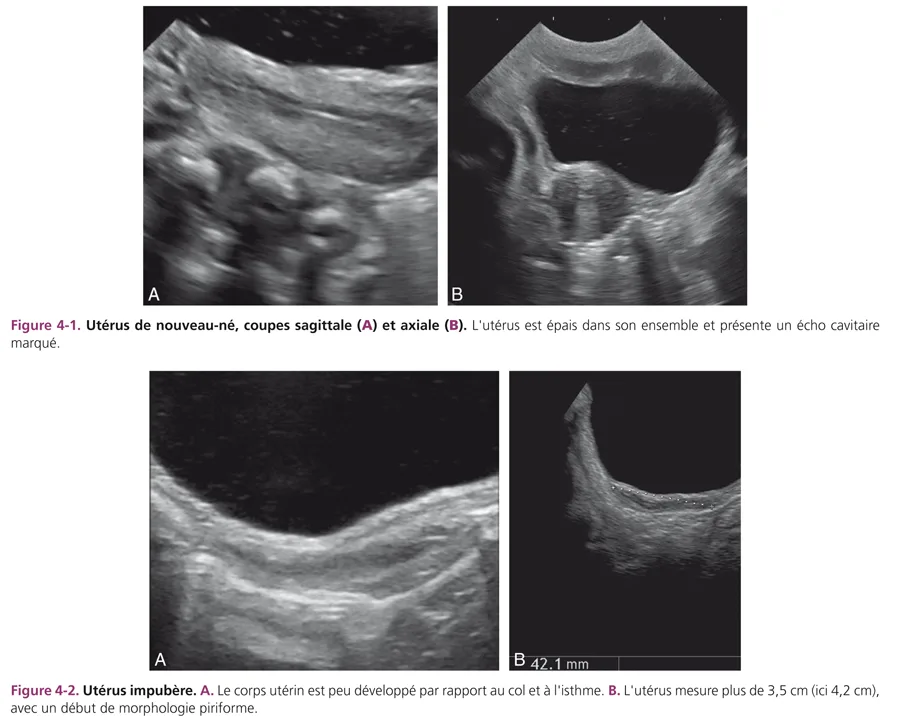

L’utérus des nouveau-nés paraît volumineux du fait de la petite taille du pelvis et de son développement transitoire dû à l’imprégnation normale maternelle pendant la grossesse. Il est épais avec un corps aussi épais que le col, mesuré de 1 à 1,5 cm (fig. 4-1). Sa hauteur est de 3,5 à 4,5 cm. La cavité utérine est soulignée par un écho dense médian, témoin d’un léger développement de l’endomètre. Le vagin sous-jacent présente des parois musculaires hypoéchogènes épaisses, bien visibles. Cet aspect de gros utérus à la période néonatale disparaît en quelques semaines ou mois pour adopter la morphologie impubère normale [1–3]. L’utérus impubère a une morphologie particulière « en goutte » avec un corps utérin fin par rapport au col et à l’isthme plus épais, formant les deux tiers du volume utérin (fig. 4-2A). Le rapport corps sur col est inférieur à 1. La hauteur utérine est mesurée à 3 cm ± 0,5 cm. La taille et l’aspect de l’utérus restent inchangés jusqu’à l’âge de 8 à 9 ans. Son échostructure est hypoéchogène, homogène. La ligne cavitaire n’est pas visible. Un fin écho cavitaire est parfois vu au niveau du col. Les parois vaginales sont fines.